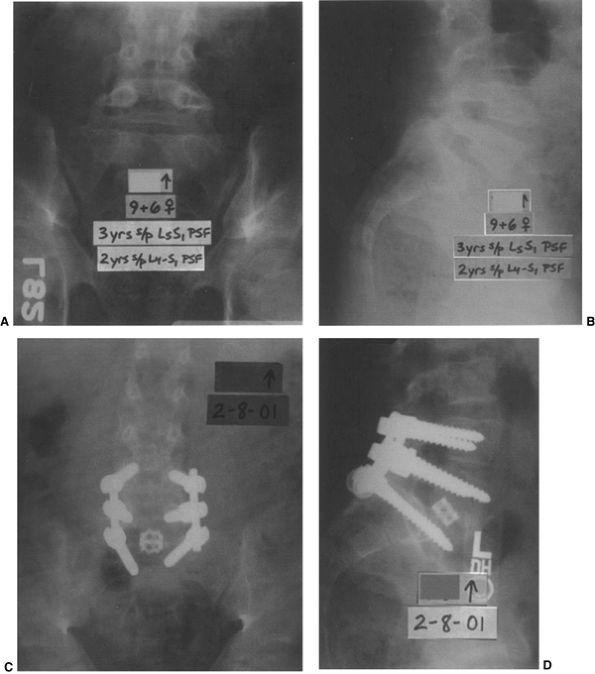

![]() |

Figure 21.12 A and B: The patient is a girl 9 years and 6 months old who has undergone two prior in situ

fusions for a low-grade isthmic dysplastic spondylolisthesis at L-5–S1. She ultimately developed a solid fusion at L-4–L-5, and pseudarthrosis at L-5–S1, with continued lumbosacral pain. C and D: She then underwent a posterior instrumented revision fusion from L-4 to the sacrum as well as an anterior interbody fusion with a structural cage and bone graft at L-5–S1 in an attempt to alleviate the pain caused by her pseudarthrosis. |